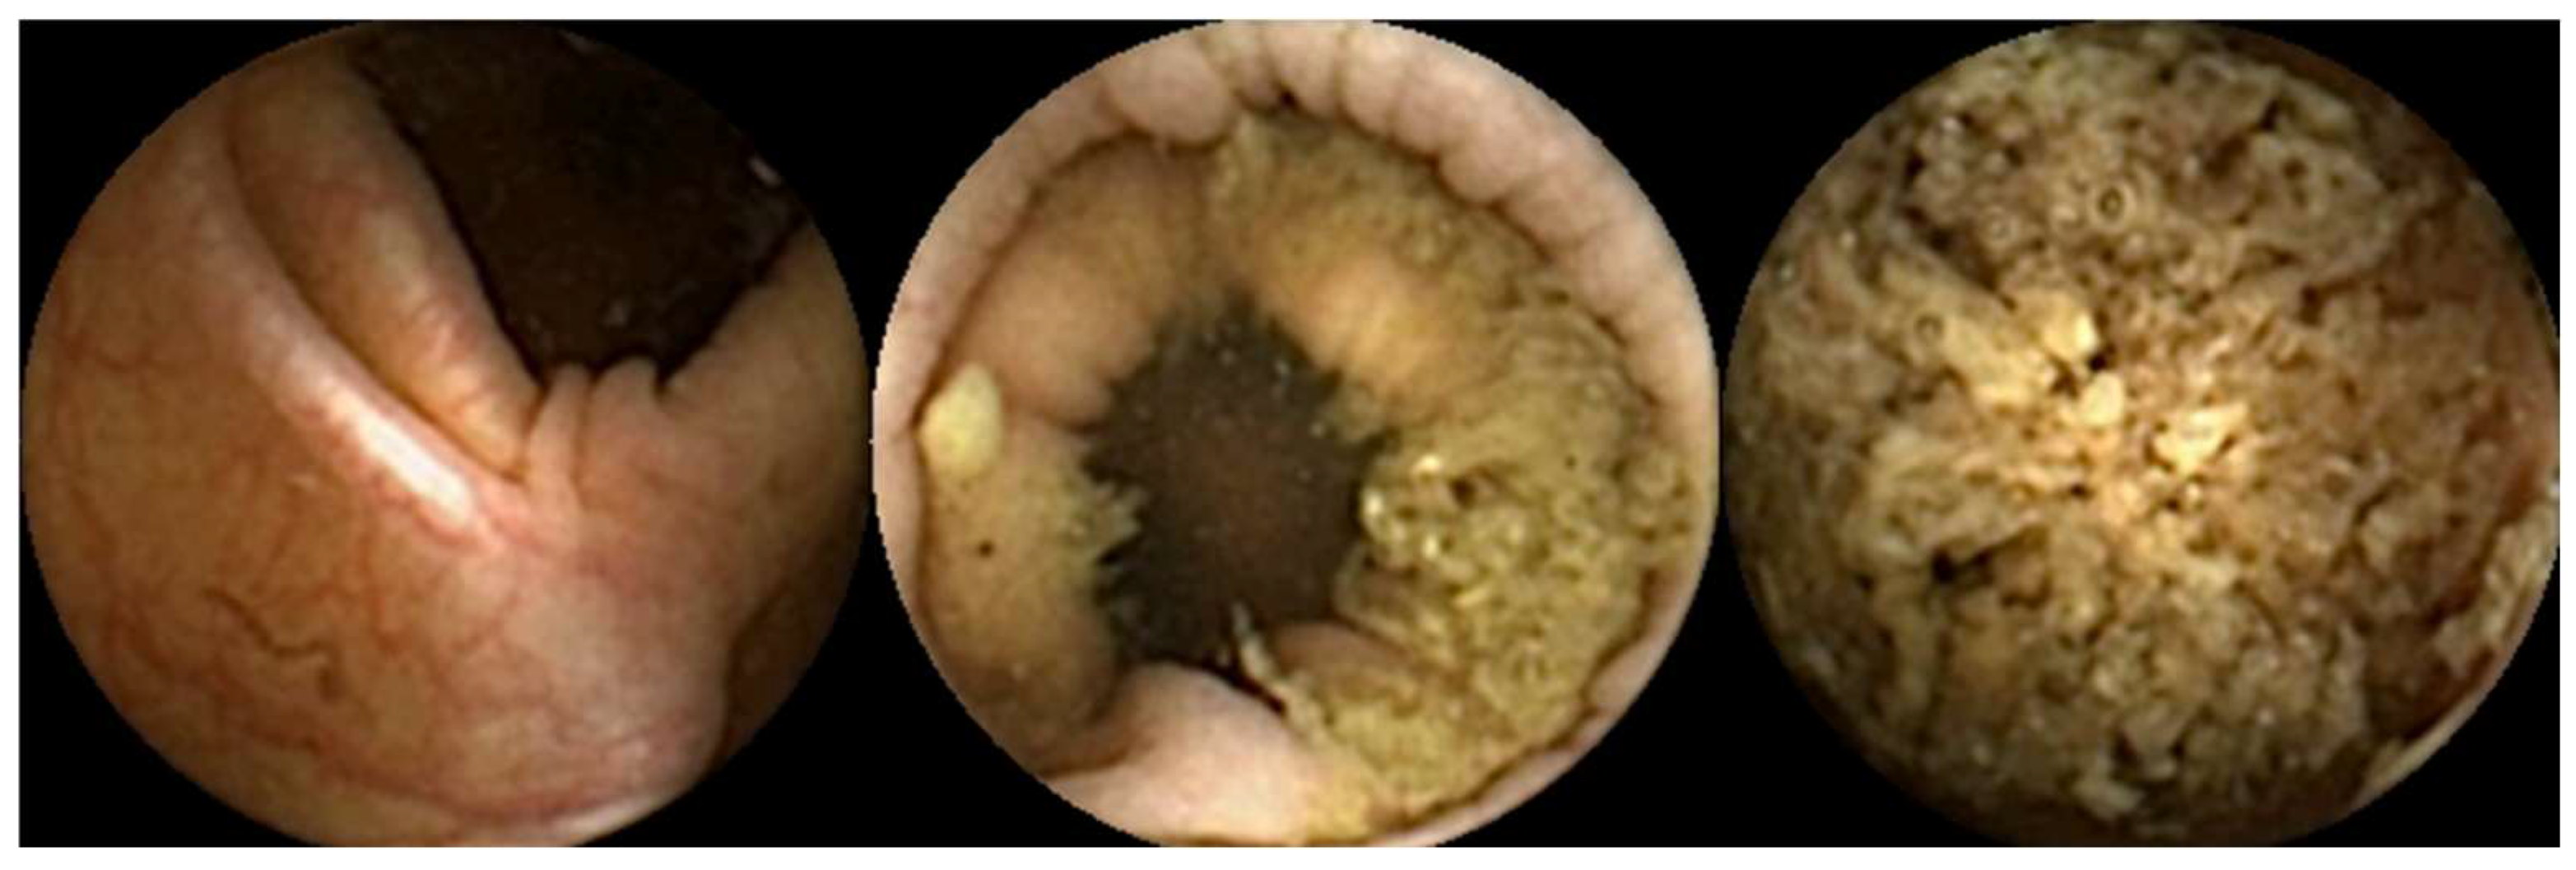

- Ribeiro, T.; Mascarenhas, M.; Afonso, J.; Cardoso, H.; Andrade, P.; Lopes, S.; Ferreira, J.; Mascarenhas Saraiva, M.; Macedo, G. Artificial intelligence and colon capsule endoscopy: Automatic detection of ulcers and erosions using a convolutional neural network. J. Gastroenterol. Hepatol. 2022, 37, 2282–2288. [Google Scholar] [CrossRef] [PubMed]

- Mascarenhas Saraiva, M.; Ferreira, J.P.S.; Cardoso, H.; Afonso, J.; Ribeiro, T.; Andrade, P.; Parente, M.P.L.; Jorge, R.N.; Macedo, G. Artificial intelligence and colon capsule endoscopy: Automatic detection of blood in colon capsule endoscopy using a convolutional neural network. Endosc. Int. Open 2021, 9, E1264–E1268. [Google Scholar] [CrossRef]

- Mascarenhas, M.; Ribeiro, T.; Afonso, J.; Ferreira, J.P.S.; Cardoso, H.; Andrade, P.; Parente, M.P.L.; Jorge, R.N.; Mascarenhas Saraiva, M.; Macedo, G. Deep learning and colon capsule endoscopy: Automatic detection of blood and colonic mucosal lesions using a convolutional neural network. Endosc. Int. Open 2022, 10, E171–E177. [Google Scholar] [CrossRef]